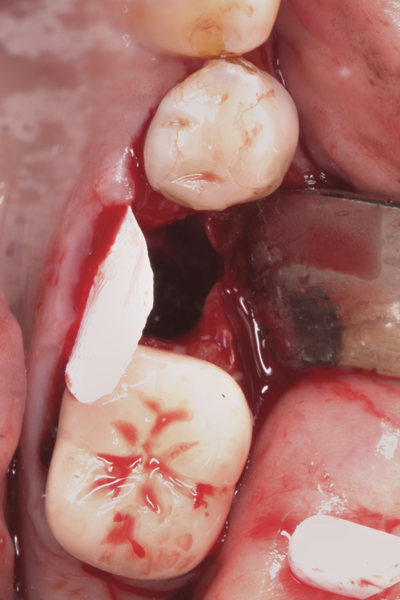

The four presented cases shown in Figure 1 through Figure 25 were all treated in a similar manner as outlined in detail in the captions for the first case (Figure 1 through Figure 11). In all four cases, teeth with pathosis were removed, buccal and lingual flaps were elevated, and sites were surgically debrided. A Cytoplast d-PTFE barrier was sized and inserted usually under the buccal flap, the bone graft was added, the barrier was then tucked under the lingual flap, and the flaps were sutured. Bone grafts were used in all of the cases, because buccal bony plates were resorbed and the bone graft helped support the barrier.

Fig 12. (Case 2) Tooth No. 9 was extracted; the buccal plate was dehisced.

Figure 12

Fig 13. Flap elevated 6 months after d-PTFE barrier and bone graft were placed; the barrier was removed after 4 weeks. This photograph shows the buccal plate regenerated.

Figure 13

Fig 14. An implant was inserted in regenerated bone.

Figure 14